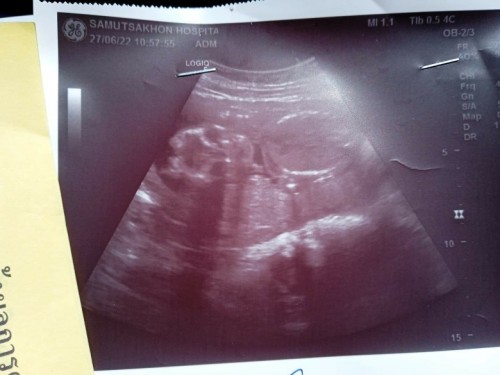

น้องได้ 26+2 week น้ำหนัก1089 ไปซาวแร้วปากน้องเปนแบบนี้จะเปนอะไรไหมคะ..แม่แอบกังวล🥺🥺

อาจจะอยู่ที่มุมนะคะะเม่ ตอนเราซาวด์ก็ประมาณนี้ค่ะ ตอนนั้นเรากังวลเหมือนกันว่าน้องจะเป็นไรมั้ย เเต่คลอดเเล้วปกติดีค่ะ ไม่ต้องกังวนนะคะเเม่ อาจจะอยู่ที่มุมภาพ

คุณหมอได้บอกไหมคะ บางครั้งอาจจะเป็นที่มุมภาพคะ อีกสัก2สัปดาห์ลองอัลตร้าซาวใหม่คะ น้องจะเปลี่ยนท่านอนต้องดูหลายๆมุมคะ

ถ้าหมอไม่บอกอะไรน่าจะไม่มีอะไรน่าห่วงนะคะ อาจจะมุมภาพ รึลูกกำลังเล่นยุ

ถ้าหมอไม่แจ้งความผิดปกติน่าจะปกตินะคะ อาจจะเป็นน้องอ้าปากพอดีมั้ยคะ